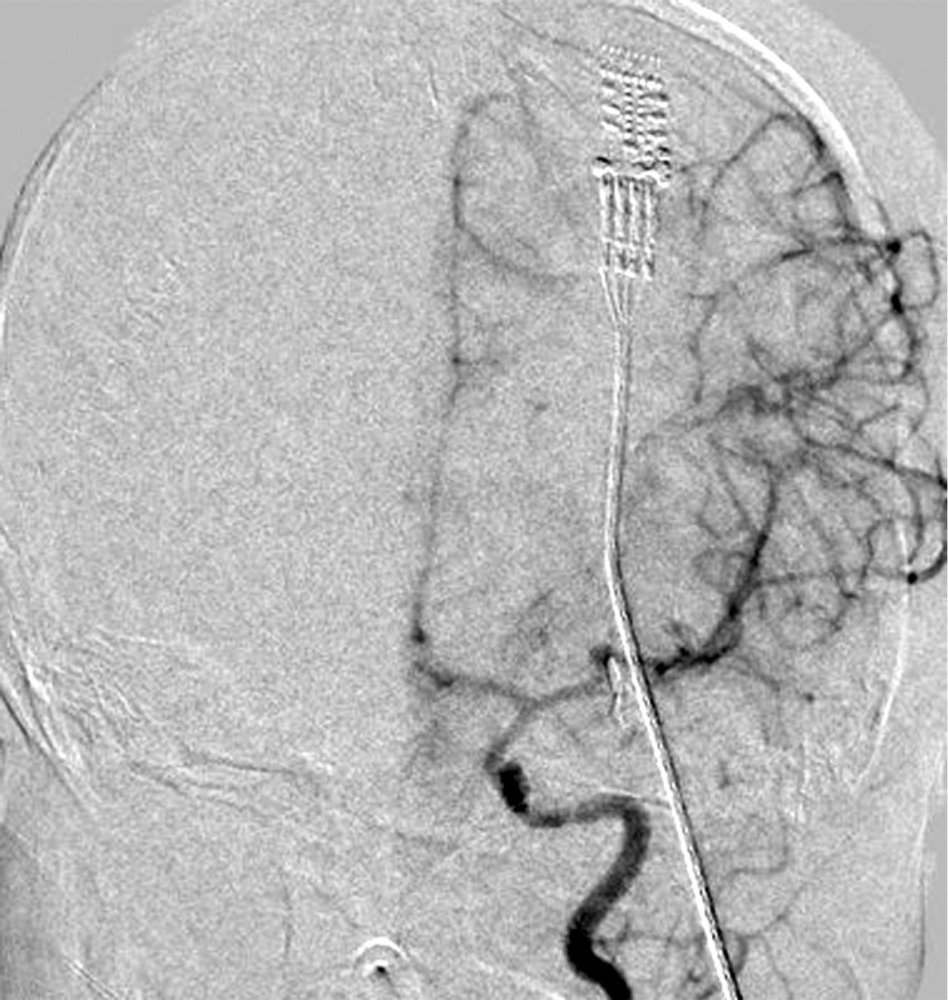

при которой отмечены выраженный отек и формирование обширного очага ишемии в левом полушарии. Желудочковая система и базальные цистерны прослеживались. Для проведения дифференциальной диагностики вазоспазма и постдислокационных нарушений кровообращения была выполнена прямая ангиография, по результатам которой выраженный ангиоспазм в левом каротидном бассейне не был подтвержден (рис. 4).

В описанном нами случае возникновение и динамика вазоспазма изначально оценивались с помощью ТКДГ. Начиная со 2-х суток после разрыва аневризмы было отмечено нарастание ЛСК. На 3-и сутки после нейрохирургического вмешательства при повторной КТ была выявлена зона постишемического отека в левом полушарии. Для верификации причин развития ишемии была выполнена прямая ангиография, по данным которой спазм сосудов не был выражен. Вероятно, формирование ишемического очага было следствием дислокационного синдрома.